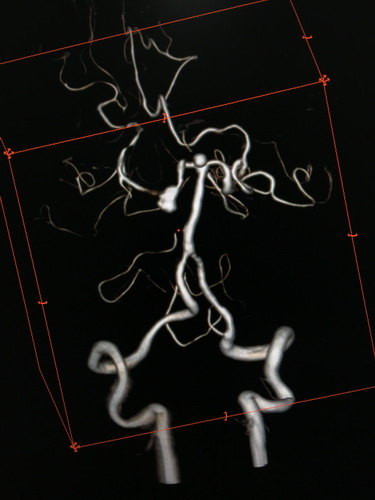

全脑血管造影提示:左侧颈内动脉主干血管明显狭窄,大脑中动脉及前动脉基本闭塞,左侧供血差,颈外动脉有少量代偿,左侧椎动脉造影示右侧大脑后动脉P2段夹层、基底动脉顶端,分别大小为6 mmX5mmX4mm瘤颈约5mm;4 mmX4mmX3mm瘤颈约3mm。

3D成像